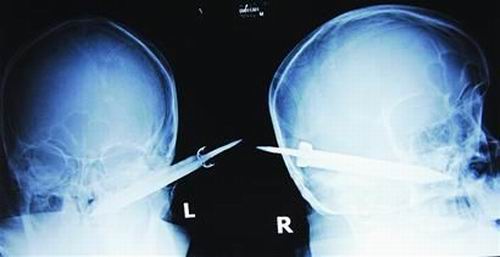

經(jīng)過檢查,醫(yī)生說這把長有10厘米左右的刀,從右耳窩上前方直接刺進了鼻腔,離頜內(nèi)大動脈很近,刀卡在了骨頭中,要取出這把刀最怕大出血,萬幸的是這把三棱刀并沒有傷及大腦。

截至昨晚11時30分,患者頭部刀經(jīng)手術已取出,生命體征平穩(wěn)。(芮瀟瀟)